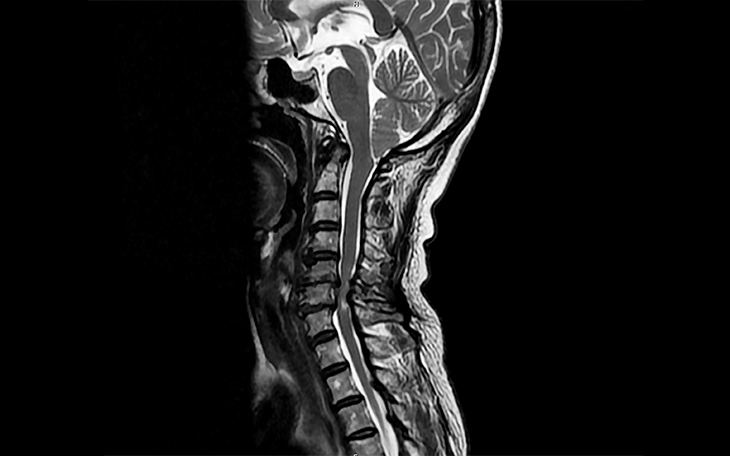

Ein einfaches Röntgenbild der Wirbelsäule zeigt nur die Knochenstruktur, nicht jedoch die Bandscheiben oder Nerven. Für eine exakte Diagnose wird daher ein MRT (Magnetresonanztomographie) empfohlen. Es ist nicht-invasiv und zeigt die betroffene Bandscheibe deutlich. Vor der Verfügbarkeit des MRT wurden CTs oder Myelogramme genutzt. Bei Patienten mit Herzschrittmachern, die kein MRT machen dürfen, müssen diese Verfahren weiterhin eingesetzt werden.

Konventionelle Röntgenaufnahmen sind zur Ersteinschätzung wichtig. Bei instabilen oder nicht verschobenen Frakturen kann eine CT nötig sein. Ein MRT ist essenziell zur Beurteilung von Rückenmark, Bändern und Weichteilen und sollte möglichst vor einem operativen Eingriff erfolgen.

Einfache Röntgenbilder zeigen keine Spinalkanalverengung, da sie nur Knochenstrukturen abbilden. Sie können jedoch auf begleitende Arthrose hinweisen. Die Methode der Wahl ist die Magnetresonanztomografie (MRT), mit der sich Ausmaß und Lokalisation der Einengung genau darstellen lassen – ohne Strahlen oder Kontrastmittel.

Die Diagnose basiert auf einer gründlichen Anamnese und körperlichen Untersuchung. Röntgenbilder können Arthrose zeigen, liefern jedoch keine ausreichenden Informationen zur Rückenmarkskompression. Eine MRT ist das Mittel der Wahl zur Beurteilung des Ausmaßes der Stenose. Bei Patienten mit Herzschrittmacher oder MRT-Kontraindikationen sind CT-Myelogramme eine Alternative.